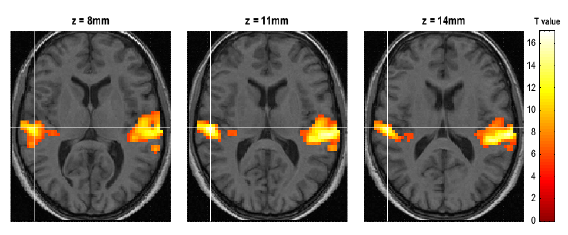

30.4 Inference ..........................................231

30.4.1 Contrast manager ................................235

30.4.2 Masking ......................................235

30.4.3 Thresholds ....................................235

30.4.4 Files ........................................236

30.4.5 Maximum Intensity Projections .........................236